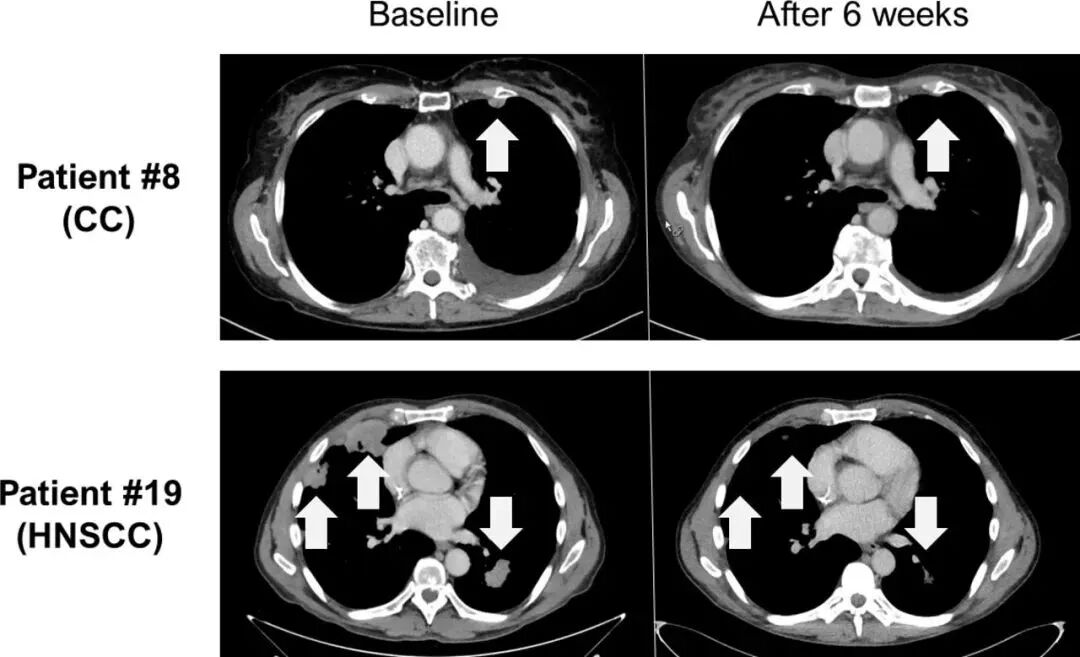

▼两例达到部分缓解(PR)患者TIL细胞治疗前后的计算机断层扫描(CT)扫描图像

注:图中显示了胆管癌患者8、HNSCC患者19的基线和细胞输注6周后的图像。